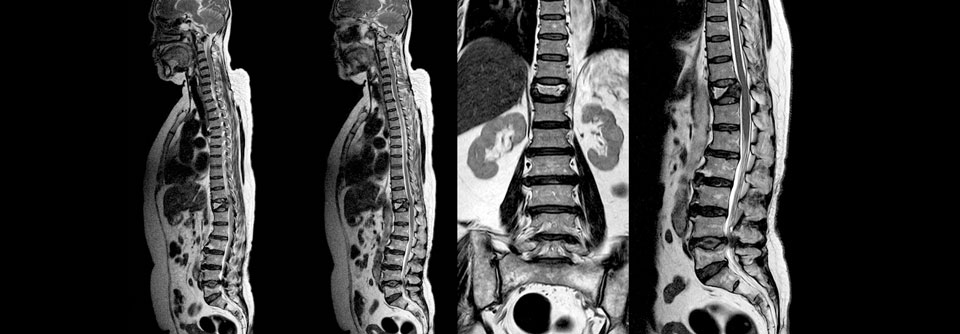

Osteoporose mit Kyphose sowie eingebrochenen und höhenverminderten Wirbelkörpern (kolorierter 3D-Scan). Osteoporose mit Kyphose sowie eingebrochenen und höhenverminderten Wirbelkörpern (kolorierter 3D-Scan). © Science Photo Library/Fung, K.H.